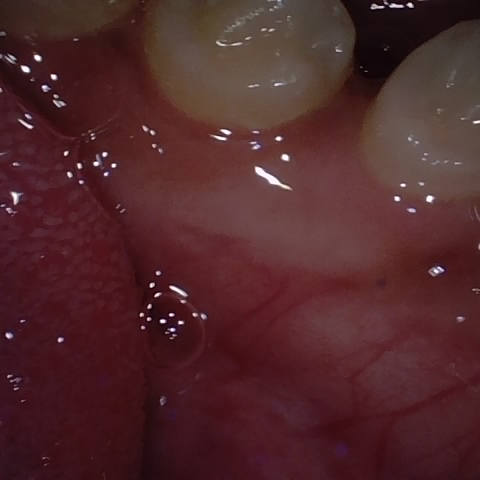

NHD25466

Annotated as "Good"

Original Image Rendering Image